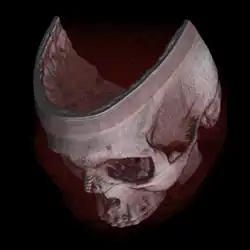

For example, a volume may be viewed by extracting isosurfaces (surfaces of equal values) from the volume and rendering them as polygonal meshes or by rendering the volume directly as a block of data. The marching cubes algorithm is a common technique for extracting an isosurface from volume data. Direct volume rendering is a computationally intensive task that may be performed in several ways.

Volume rendering is distinguished from thin slice tomography presentations, and is also generally distinguished from projections of 3D models, including maximum intensity projection.[1] Still, technically, all volume renderings become projections when viewed on a 2-dimensional display, making the distinction between projections and volume renderings a bit vague. Nevertheless, the epitomes of volume rendering models feature a mix of for example coloring[2] and shading[3] in order to create realistic and/or observable representations.